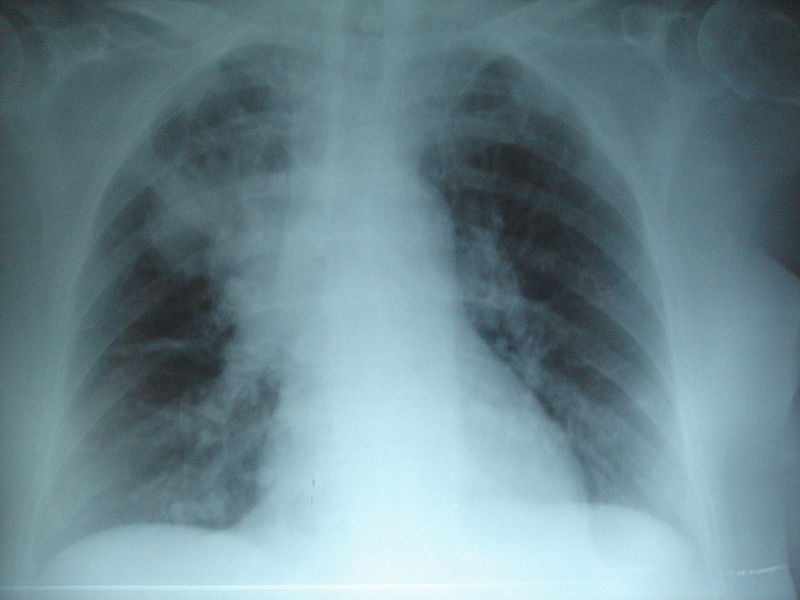

Neumonia por Klebsiella pneumoniae....